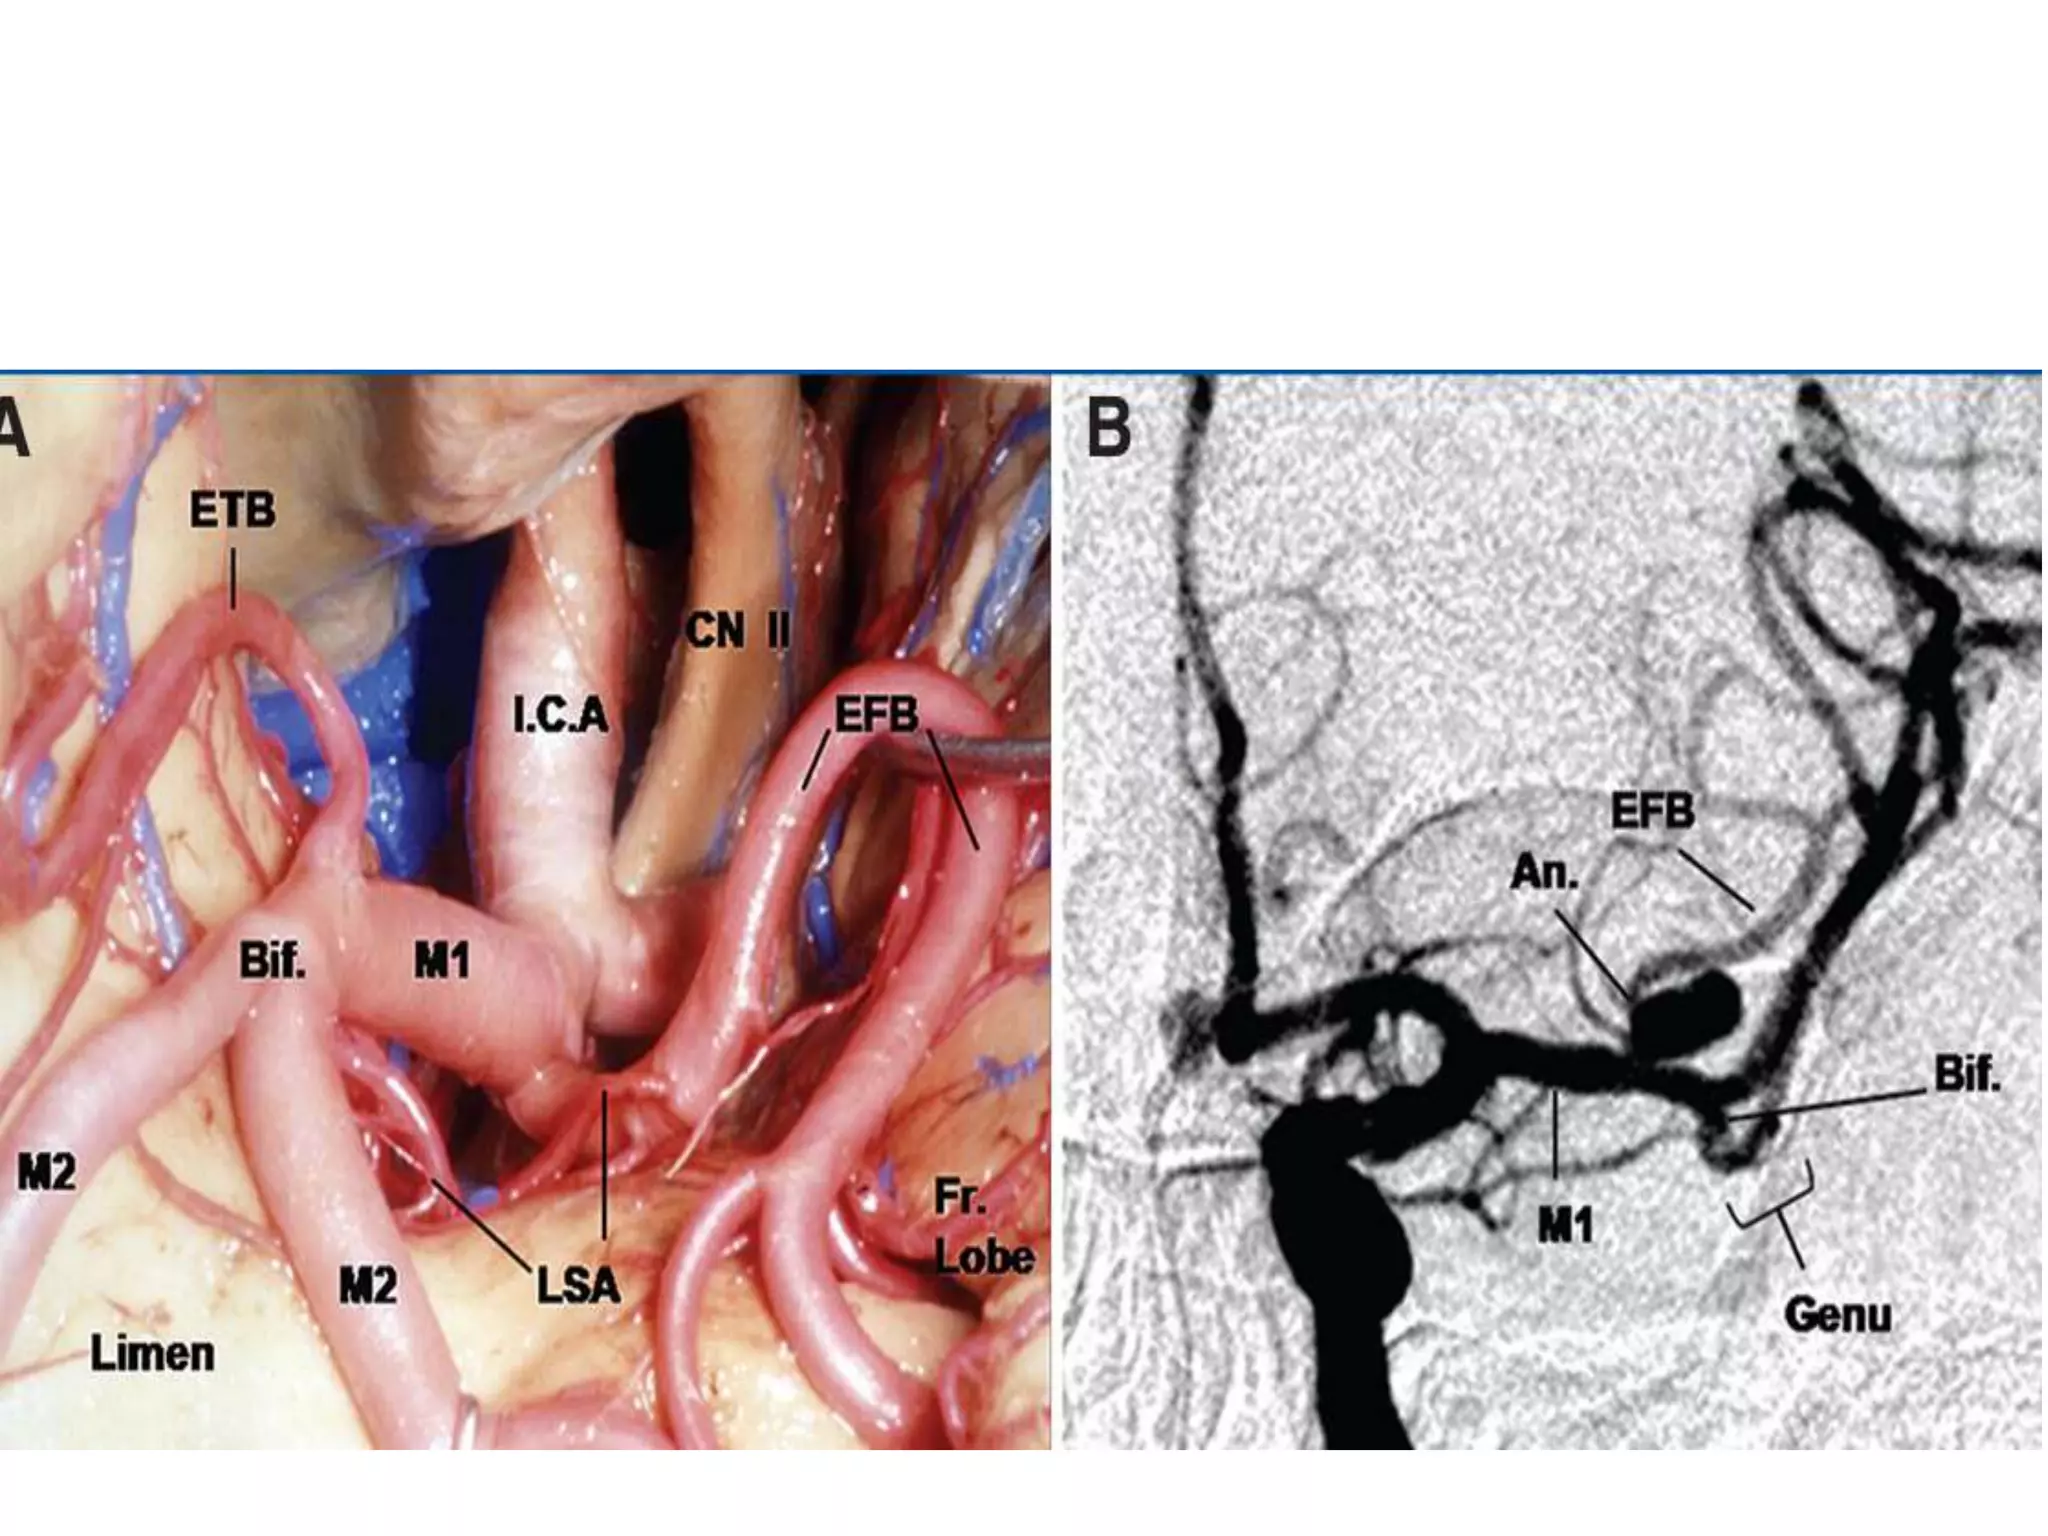

M1 segment

• Microneurosurgical and

angiographic

• Prebifurcation and post

bifurcation parts

• How to distinguish between early

branches and M1

M1 segment • Microneurosurgicaland angiographic • Prebifurcation and post bifurcation parts • How to distinguish between early branches and M1

Perforating branches

• Lenticulostraite arteries - branches of MCA that

enter anterior perforating substance (APS)

• origin from superior or posterosuperior MCA

• 3 groups : medial, intermediate and lateral

• MEDIAL: least constant, 1-5 branches from M1, enter

medial APS

• INTERMEDIATE: constant, few branches dividing,

atleast 1 major artery

• LATERAL: constant S shaped course, enter

posterolateral part of APS

Perforating branches • Lenticulostraitearteries - branches of MCA that enter anterior perforating substance (APS) • origin from superior or posterosuperior MCA • 3 groups : medial, intermediate and lateral • MEDIAL: least constant, 1-5 branches from M1, enter medial APS • INTERMEDIATE: constant, few branches dividing, atleast 1 major artery • LATERAL: constant S shaped course, enter posterolateral part of APS